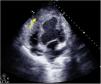

Tras una semana en lista urgente 0A, inestabilidad hemodinámica con necesidad de aumento de soporte farmacológico evidenciándose en la ecografía transtorácica rotura de hematoma contenido apical (fig. 2, flecha amarilla). Ante shock hemorrágico refractario a medidas, se programa cirugía urgente para control del sangrado; sin embargo, de forma coincidente, disponibilidad de órgano compatible con nuestro paciente, por lo que finalmente se realiza trasplante cardíaco.